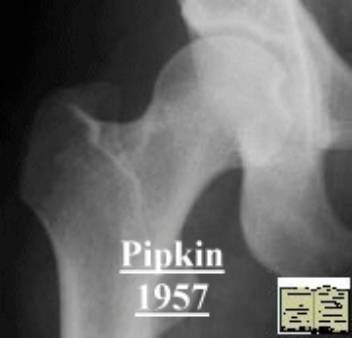

Pipkin骨折

股骨头骨折伴髋关节后脱位。常见于屈膝屈髋位汽车仪表盘损伤。